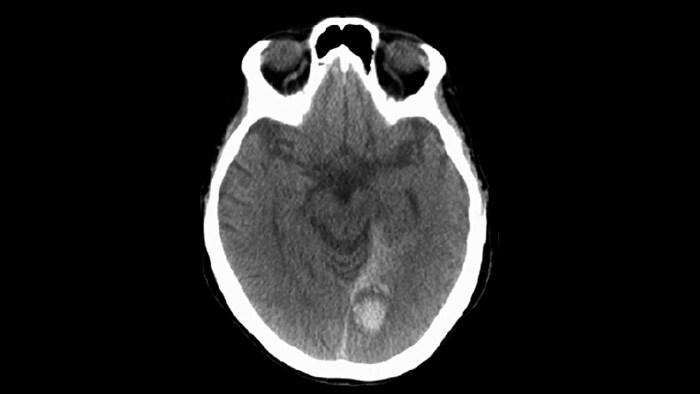

SmartCT Soft Tissue撮影にて、出血の有無等、治療後の確認を行います。